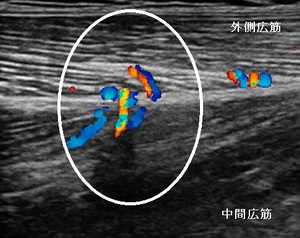

右もも外側部 超音波長軸像 左同部 超音波長軸像

当接骨院での初診時は、深く膝を曲げることができず、患部の圧痛や熱感が著明でした。超音波観察を

行ったところ、右大腿四頭筋の外側広筋と中間広筋の損傷部に血流が増勢し、内出血と浮腫が認められました

(左上画像の丸の囲み)。